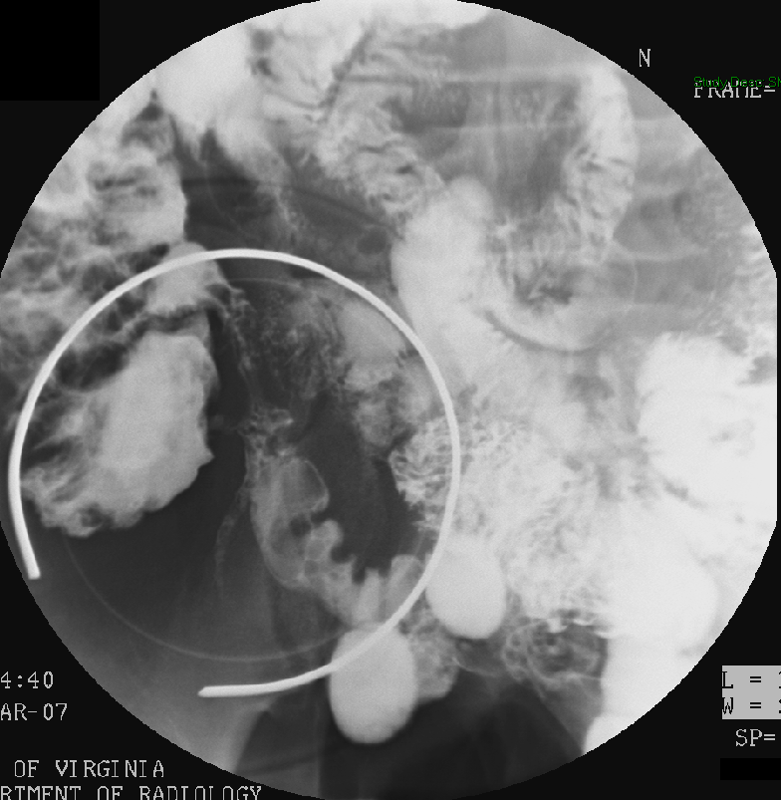

- The gynecologist will begin injecting contrast material into the uterus. Obtain images periodically throughout the procedure (usually at the direction of the gynecologist). The images should include the uterine cavity filled with contrast material, bilateral fallopian tubes filled with contrast material, and spillage and dispersion of contrast material into the peritoneal cavity (image 1) (image 2) (image 3) (image 4) (image 5).

- It may be necessary to place the patient into either the right lateral or left lateral oblique postion to define the anatomy more clearly.